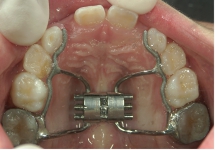

急速拡大装置(きゅうそくかくだいそうち)

2週間かけて、上顎の骨のつなぎ目を急速に広げる装置です。1日2回、中央についている拡大調節ネジを調整することで、強い力で歯列を押し広げます。永久歯に生えそろってから、あまり時間のたっていない20歳くらいまで効果がみられます。